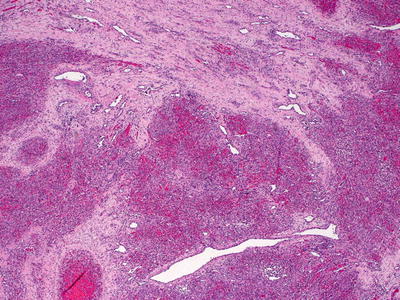

21.6.6.2 Histology

KHE is comprised of diffuse nodular proliferations of slit-like vessels surrounded by endothelial cells (Figs. 21.33 and 21.34). In some areas, the vessels are well formed, whereas in other areas, the vessels are poorly formed and have an infiltrative growth pattern, strongly mimicking Kaposi’s sarcoma [222]. Areas of dense cellularity comprised of endothelial cells and pericytes, and no apparent vascular differentiation may also be encountered. These areas may have a glomeruloid growth pattern [225]. Cytologic atypia is slight, and mitoses are infrequent and without atypical forms [226] (Fig. 21.35). Hemosiderin and hemorrhage are present in some cases [226]. These tumors occupy the entire dermis and can extend into the subcutaneous fat. Lateral and deep to the central tumor, large malformed lymphatic channels are present in more than half of the described cases [222, 225, 226]. Immunostaining shows that the neoplastic cell population consists of lymphatic endothelial cells as evidenced by focal staining with the lymphatic marker D2-40 [225](Figs. 21.36 and 21.37). KHE is often associated with Kasabach–Merritt syndrome, and extensive intravascular thrombus formation is observed in such cases [222]. The tumor has a propensity for local recurrence and persistence, although distant metastasis appears to be uncommon [216, 225, 227].

Fig. 21.33

A lobular configuration of dense cellularity and vascular differentiation characterizes KHE